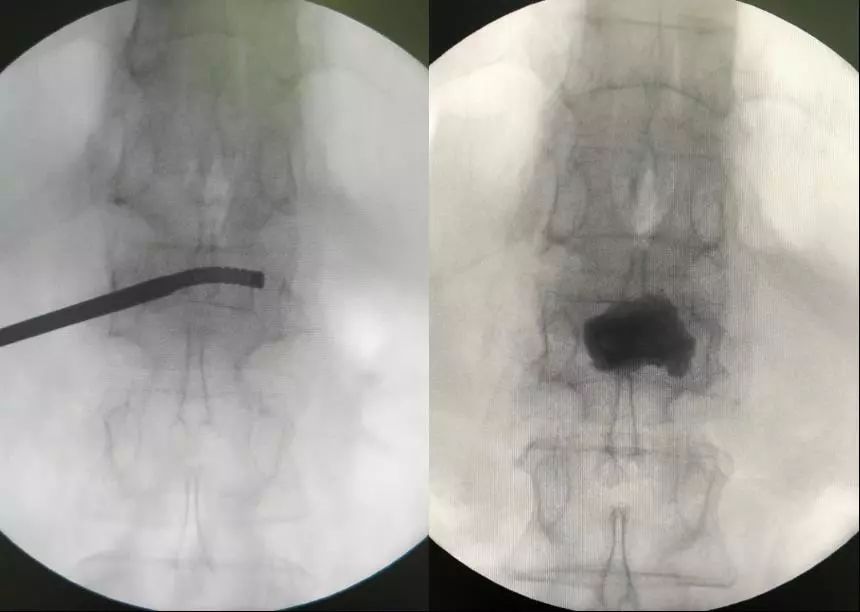

´Ë´ÎÊÖÊõʹÓûúеÈËÍýÏëµ¥²à´©´ÌÑü1×ó²àõè¾¶£¬£¬£¬£¬£¬£¬Çпª0.5cmƤ·ô£¬£¬£¬£¬£¬£¬ÔÚ»úе±ÛÖ¸µ¼Ï¾«×¼ÖÃÈëµ¼Õ롢ͨµÀÖÁ×µÌåÄڵİÐλÖ㬣¬£¬£¬£¬£¬°²ÅÅ¿ÉÍäÇúÇòÄÒ¾ÙÐж¨µãÀ©ÕÅÅòÕÍ£¬£¬£¬£¬£¬£¬Ë³ËìÍê³É¿ÉÍäÇúµ¥²àPKPÊÖÊõ£¨Í¼1-4£©¡£¡£¡£¡£¡£

ͼ3£¬£¬£¬£¬£¬£¬ÍÆ×¢¹ÇË®Äà

ͼ4£¬£¬£¬£¬£¬£¬µ¥²à´©´ÌÖÁ×µÌå¶Ô²à½¨É軡ÐÎͨµÀ£¬£¬£¬£¬£¬£¬¹ÇË®ÄàÂþÑÜÓÅÒì